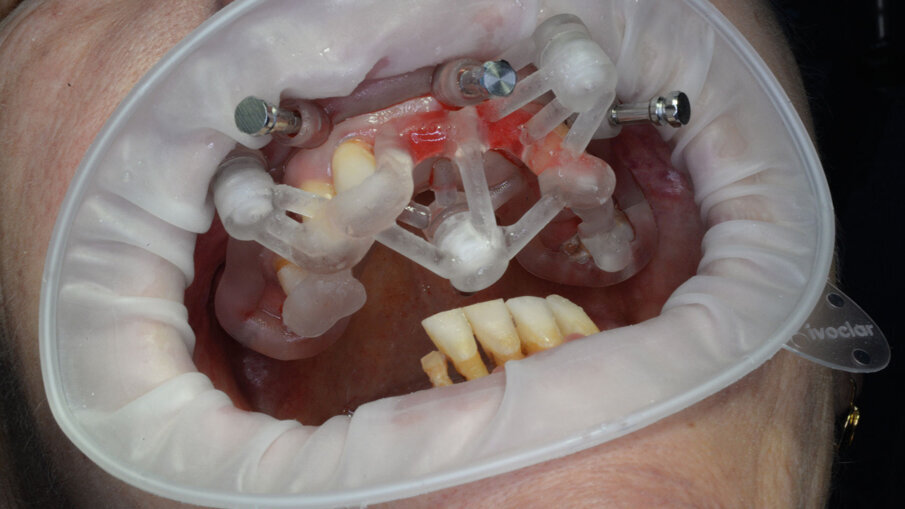

Per la realizzazione delle dime chirurgiche abbiamo utilizzato il nuovo modulo Sculpt rilasciato per lo stesso software di chirurgia guidata BNX 3D GUIDE. Questo nuovo modulo permette di creare una serie di dime scomposte da utilizzare in sequenza per eseguire le estrazioni e l’osteoplastica necessaria, rimanendo sempre all’interno di un flusso di lavoro guidato. Le dime si adattano l’una all’altra grazie a supporti di accoppiamento che contengono piccoli magneti con polarità opposta. L’azione di questi magneti permette di ritrovare velocemente e fedelmente sempre la stessa posizione delle dime anche se dovessimo rimuoverle per poi reinserirle. Affidandoci alla stabilità ancora presente su alcuni denti abbiamo progettato una prima dima ad appoggio dentale che permettesse il corretto posizionamento della dima esterna che sarà l’unica a rimanere sempre in posizione fino alla fine dell’intervento (Fig. 9). Una volta stabilizzata con i pin di stabilizzazione e rimosso il posizionatore, si è potuto apprezzare la bellezza della metodica che permette un’ampia visione e molto spazio a disposizione per poter eseguire le fasi chirurgiche preliminari di preparazione (estrazioni e sollevamento di piccoli lembi). Liberata l’arcata dall’ingombro dei denti e di tessuti in eccesso si è potuto posizionare la dima di perforazione nella corretta posizione grazie alla presenza della dima esterna rimasta in posizione (Figg. 10-13).

Alla preparazione dei tunnel implantari è seguito il loro inserimento sempre con tecnica guidata utilizzando gli appositi montatori forniti nel kit, avendo cura di far combaciare le tacche di riferimento dei montatori con le linee di repere preventivamente disegnate sulla dima così da ottenere il corretto posizionamento dei 2 mua angolati previsti nel settore anteriore (Fig. 14). In fase chirurgica il posizionamento dei mua è stato ulteriormente facilitato dalla presenza di un doppio esagono presente all’interno dell’impianto che rende possibili ulteriori aggiustamenti “di fino” del componente protesico. Avvitate tutte le torrette il provvisorio è stato poi cementato con cemento duale dedicato utilizzando un foglietto di diga preforato per facilitarne la cementazione (Figg. 15, 16).